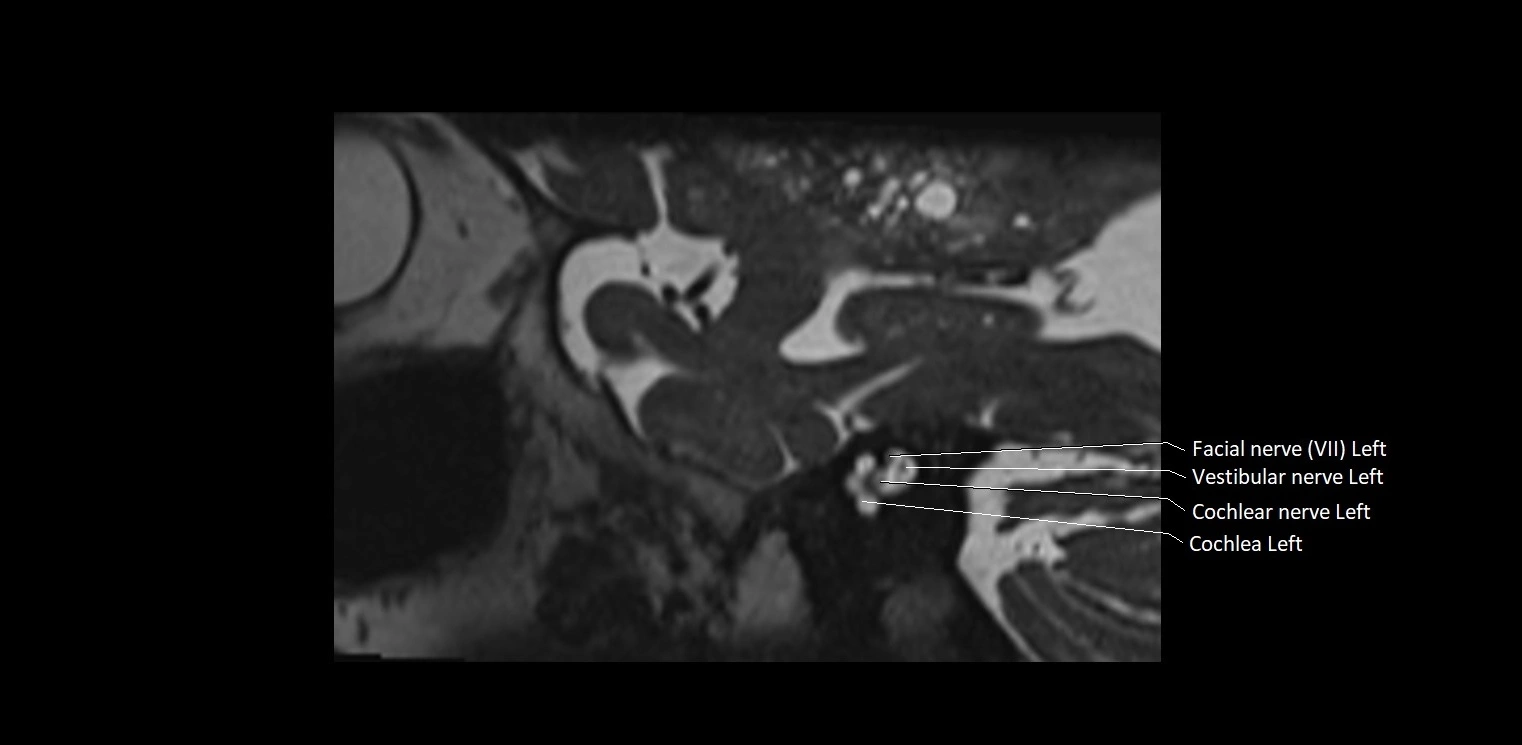

MRI images

image